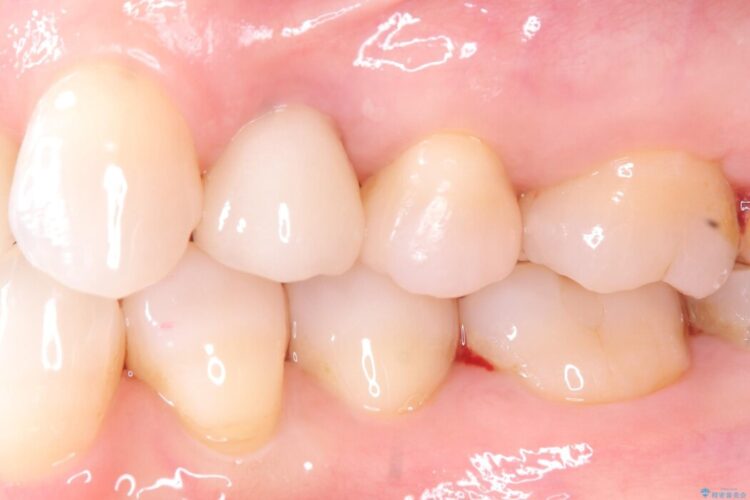

インプラント治療後は「長年悩まされた痛みから解放され、自分の歯と同じように食事ができるようになった」と喜んでいただけました。